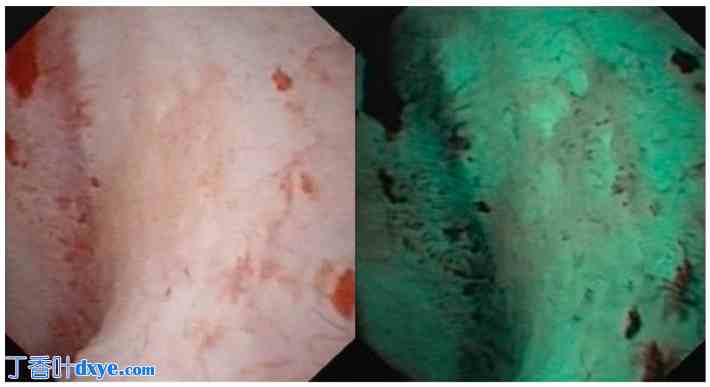

研究组患者的筛选方案包括增强CT扫描、尿液细胞学检查、腹部超声检查、膀胱镜检查和指诊输尿管软镜检查。在白光和窄带成像 (NBI) 两种模式下对整个肾盂肾盏系统(肾盂和所有肾盏)进行内镜检查,并将疑似肿瘤病变标记在图像上。可疑区域图像创建后,对两种模式下(白光或 NBI(图 1 和图 2))显示的所有病变进行活检。在此阶段,所有病例均使用活检钳(抓取钳)。在执行此阶段时,特别注意尽可能深入肾盂肾盏壁,以便获取优质样本,并最大程度地减少分期误差。

图 1.

1.jpg

肾盂肾盏肿瘤的白光和 NBI 图像。